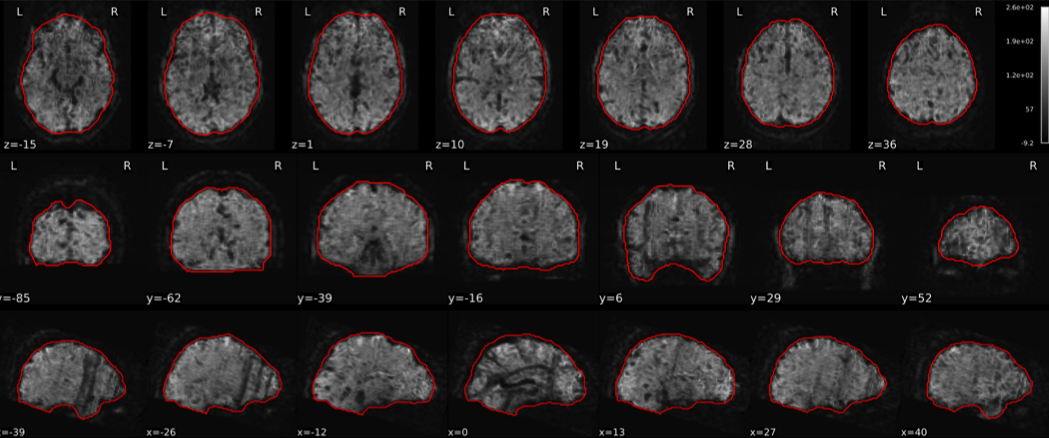

EPI tSNR

In the signal to noise ratio images of the resting state image the desired signal is compared to the amount of background noise. It is important to check all the views (sagittal, coronal, axial) because some artefacts (e.g., stripes) may be evident only in one particular view.

Example of a good subject

- Signal to noise is symmetrically distributed and there is no signal distortion

Example of a bad subject

- Asymmetry

- Potential signal distortion (might represent an artefact)

- Signal drop-out

- Stripes artefact

Clear large artefact (e.g., zebra stripes in example 1) are worth the exclusion of the subject. If you are unsure, check the other quality metrics for that subject to decide whether they should be excluded.

Summary

| good | bad |

|---|---|

| Symmetrical distribution of noise and signal | Asymmetry |

| No disruptions of the signal (no “black patches”) |

Potential signal disruptions (could be related to artefacts) |

| No stripes (sign of high motion) |

Signal drop |

| Stripe artefacts (“zebra” stripes due to motion) |